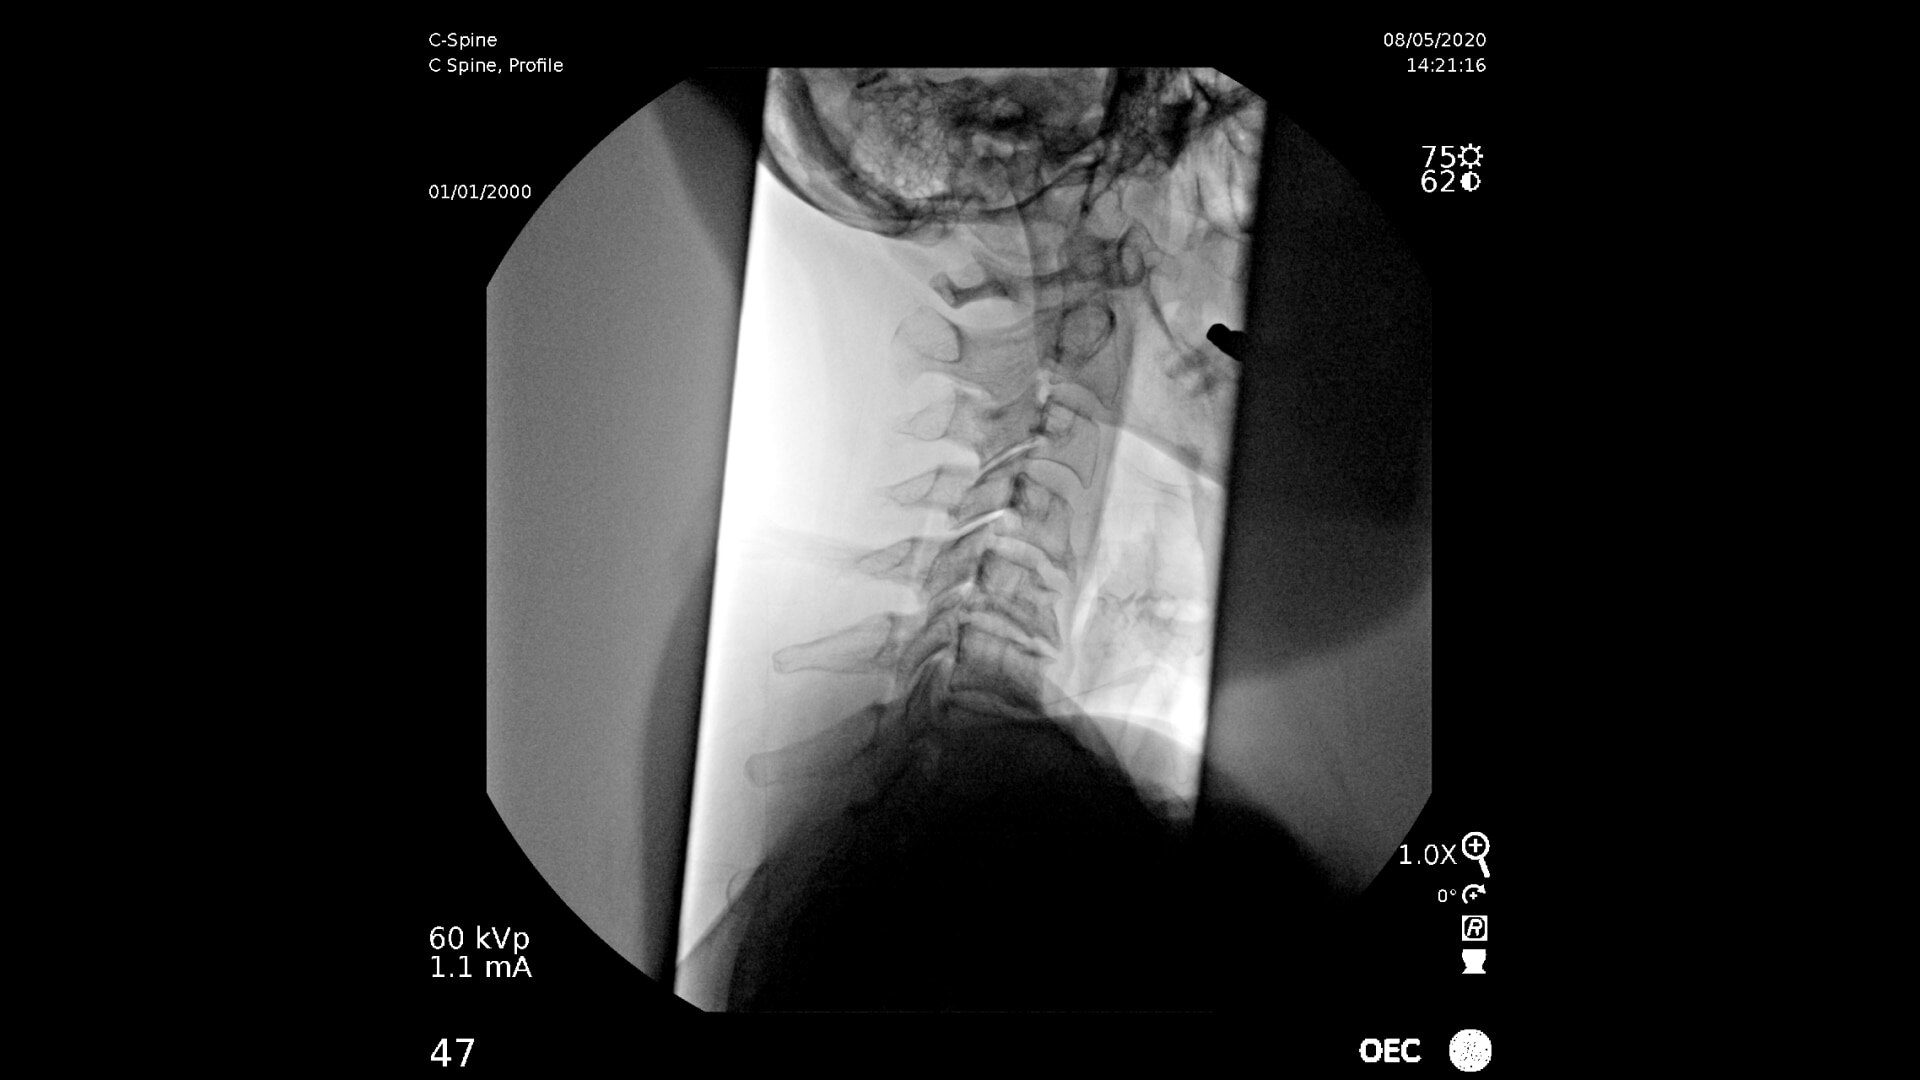

Consistently experience amazing image quality, precision, and efficiency during simple to complex pain management procedures with OEC C-arms.

Achieve precision and efficiency while experiencing the image quality needed during simple to complex pain management procedures with OEC C-arms.

See clear detail captured on a flat panel detector to a 4K display for visualization of anatomical detail.

OEC C-arms perform imaging in a variety of procedures such as:

• Cervical spine pain management